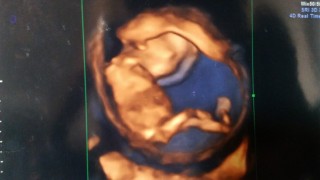

腹痛が続いてて不安だったけど、元気に手足をバタバタしてるベビを見て一安心。次は4週間後!前回に続きサイズは教えてくれなかった( ̄▽ ̄;)順調と言われたから良いけど(笑)

めちゃくちゃ元気に動いてました♪ パパも一緒だったからかな(*≧∀≦*) ちびたんもモニターの方をチラチラ(笑) めちゃくちゃ可愛かったです(*´ω`*)

4週間ぶりの受診。こんなに大きくなっていて感動してしまいました。手で顔を隠していてお顔は見れませんでしたが、4週間後も楽しみです。座高7.5センチ順調です

初めてお手手がはっきりみれました! 元気に動いていたので安心しました。 次の検診では性別わかるかな~? たのしみです!